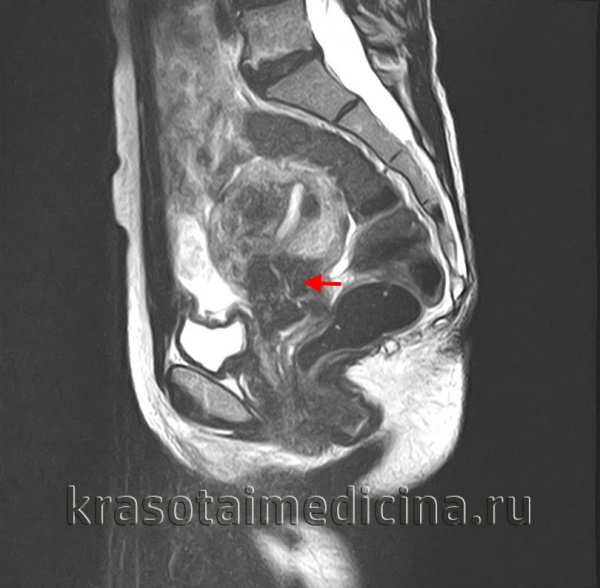

Если опухолевая инфильтрация затрагивает кишечник или мочевой пузырь, развиваются нарушения дефекации и мочеиспускания; появляется гематурия или примесь крови в кале; иногда возникают влагалищно-кишечные и влагалищно-пузырные свищи. Механическая компрессия метастатическими лимфоузлами мочеточников приводит к задержке мочи, формированию гидронефроза с последующим развитием анурии и уремии. К общим симптомам рака шейки матки относятся общая слабость, повышенная утомляемость, лихорадка, похудание.

Дополнительно при раке шейки матки проводится УЗИ малого таза, позволяющее стадировать опухолевый процесс и планировать объем вмешательства. Для исключения прорастания опухоли в смежные органы и отдаленного метастазирования прибегают к выполнению УЗИ мочевого пузыря и почек, цистоскопии, внутривенной урографии, УЗИ брюшной полости, рентгенографии легких, ирригоскопии, ректоскопии. При необходимости пациентки с выявленным раком шейки матки должны быть проконсультированы урологом, пульмонологом, проктологом.

Магнитно-резонансная томография с контрастированием является более точным методом диагностики по сравнению с УЗИ. МРТ назначается при планировании лечения и позволяет определиться с объёмом операции.